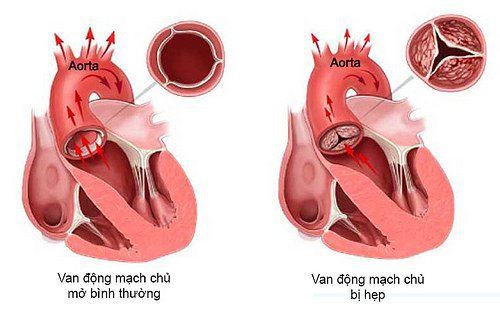

ARSA là từ viết tắt của Aberrant Right Subclavian Artery bản chất là động mạch dưới đòn phải lạc chỗ. ARSA là một biến dạng tương đối thường gặp của các nhánh của quai động mạch chủ. Động mạch chủ là một trong những mạch máu lớn vận chuyển máu từ tim đi: nó cung cấp máu giàu oxy tới đầu và thân mình.

Động mạch chủ đi ra khỏi tim, nó chạy hướng lên phía đầu, sau đó tạo nên quai động mạch chủ sau đó chạy xuống ngực và bụng. Ở hầu hết mọi người có 3 nhánh mạch máu của quai động mạch chủ đi hướng lên phía đầu, cổ và cánh tay.